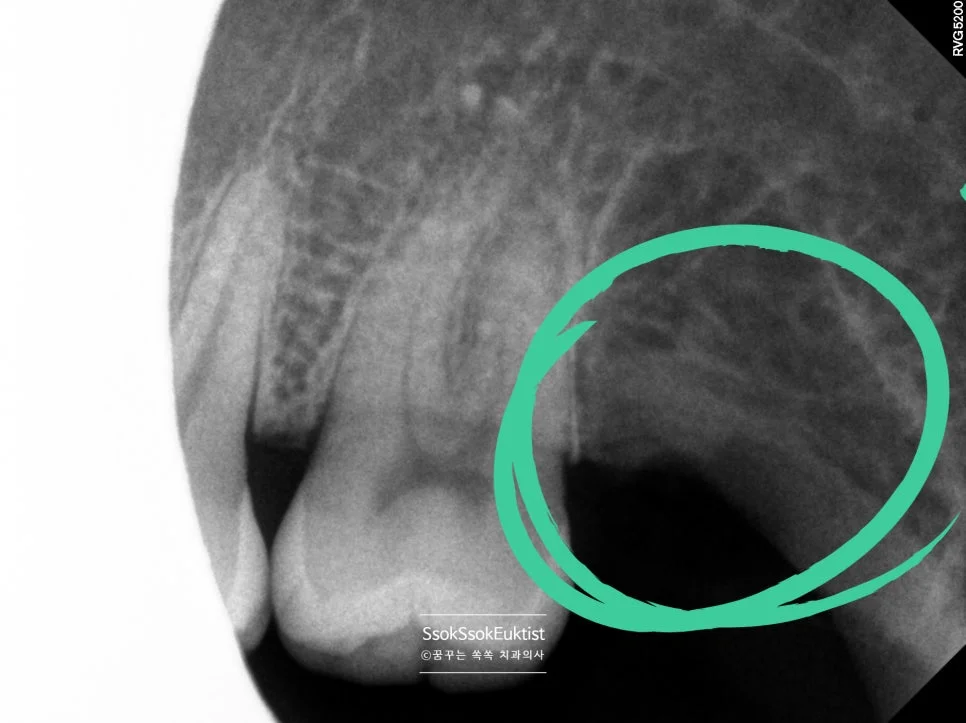

발치 완료 확인 (치근단 X-ray)

수면으로 양쪽 위아래 모든 사랑니가 당일 발치된 모습입니다.

사랑니 발치 후 우측 상악 치근단 X-ray 초록 원 표시

우측 상악 발치 완료 (초록 원)

사랑니 발치 후 좌측 상악 치근단 X-ray 초록 원 표시

좌측 상악 발치 완료 (초록 원)

사랑니 발치 후 우측 하악 치근단 X-ray 초록 원 표시

우측 하악 발치 완료 (초록 원)

사랑니 발치 후 좌측 하악 치근단 X-ray 초록 원 표시

좌측 하악 발치 완료 (초록 원)

수면으로 양쪽 위아래 사랑니 발치 후 잇몸 뼈에 남아있는 잔존 뿌리가 없으니 치료가 잘 마무리되었다고 볼 수 있겠죠 🙂